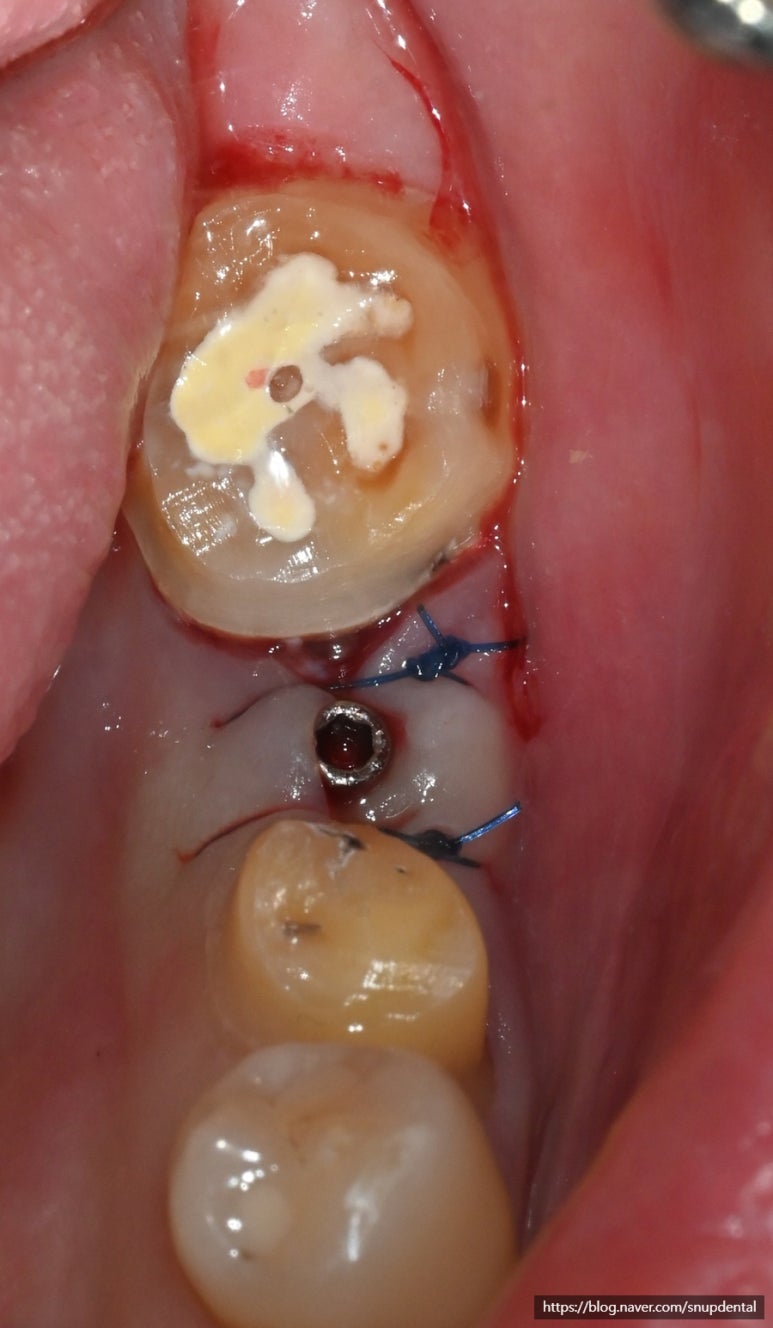

임플란트 수술 후 구강 내 사진 및 부분 CT 캡처 사진입니다

살려 쓰기로 한 작은 어금니 및 근관치료(신경치료) 한 어금니는 임시치아를 사용하면서 불편함이 없음을 확인.

맞춤형 지대주 연결 및 PMMA 임시치아 부착.

임플란트 수술 후 부분 CT 및 구강 내 사진

작은 어금니 및 두 번째 어금니는 지르코니아 최종 수복물을 임시 접착하여 사용 중입니다

THAB를 사용하여 보다 많은 부착치은이 생성될 수 있도록 유도하고 잇몸을 여는 2차 수술을 생략하도록 하였습니다.